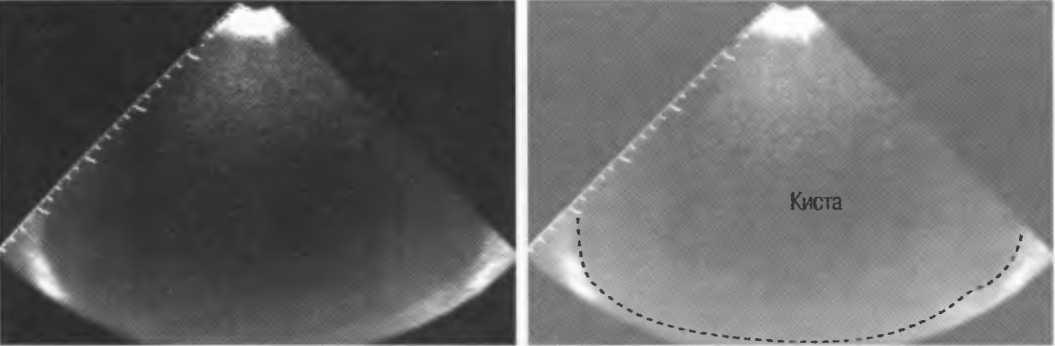

Кисты

Киста, как правило, визуализируется в виде анэхогенной зоны, при этом структуры, расположенные за кистой, обычно усилены: полость кисты анэхогенна, поскольку в ней нет структур с различным акустическим сопротивлением. В результате того что жидкость не поглощает ультразвук в такой же степени, что и ткань, эхо-сигналы от расположенных позади кисты структур гиперкомпенсированы сканером и выглядят усиленными — появляется эффект усиления задней стенки (рис. 14а,б).

Киста определяется в виде анэхогенной зоны с усилением по задней стенке. Если в кисте есть внутренние зхоструктуры, то они могут быть реальными или являться артефактами.

Рис. 14а. Заполненная жидкостью киста: полость кисты анзхогенна, имеется усиление задней стенки.

Рис.14б. Данная киста яичника имеет толстые стенки и внутренний осадок, создающий внутреннюю эхоструктуру, перемещающуюся при перемене положения тела пациента.